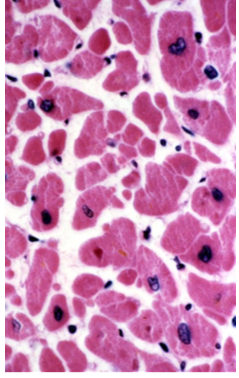

What type of muscle is this a cross section of

cardiac muscle